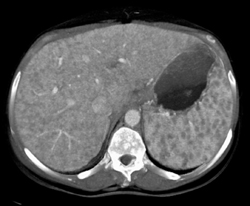

Sarcoidosis